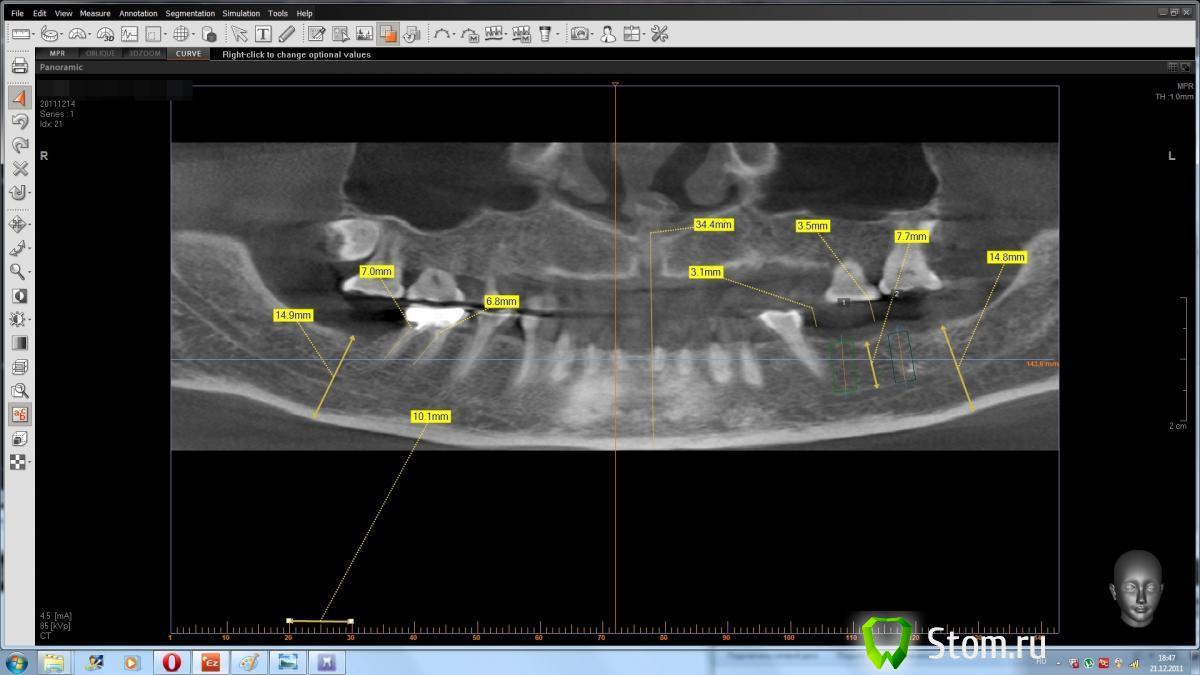

dent-a Опубликовано 21 декабря, 2011 Поделиться Опубликовано 21 декабря, 2011 Предыстория. КЛКТ на ватэке сделано в уважаемой фирме. Открыл, просчитал, получилось всё хорошо, сделал пару снэпов (фоток) рис 1. Дело было на работе вечером (windows xp). На следующий день то же самое (перепроверка) - но на домашнем компе (win 7) - открываю и результаты совсем иные рис 2 .... Сделал опять снэпшоты. Потом взял то - что просчитал днём ранее и экспортировал в планмековский считовод. Откалибровал в нём всё и .... всё оказалось верно рис 3. Где правда - то ?)) Позвонил в фирму....но там ко мне применили приём, как говорит один знакомый доцент, "мягкий посыл"... ну и на всякий им ещё в почту скинул. Раньше делал кт планмека в более дорогом месте...видимо и дальше буду делать дороже, т.к. таких аномалий не было. Поделитесь цифровым опытом. Может просто горе от ума :? Ссылка на комментарий